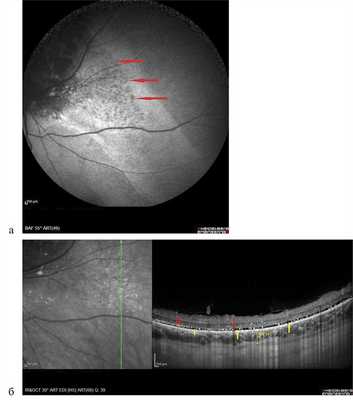

Аутофлюоресценция исследована у 6 пациентов с ГХ, опухоль была представлена участком обширной гипоаутофлюоресценции различной интенсивности (рис. 8, а), в то время как по ФАГ ей соответствовали зоны гиперфлюоресценции собственных сосудов опухоли и сосудистых лакун (см. рис. 8, б). Локальный фиброз, гиперплазия и атрофия пигментного эпителия также представлены зонами гипоаутофлюоресценции. Участки гипераутофлюоресценции соответствовали зонам скопления липофусцина в виде пятен оранжевого пигмента, описанного J. Gass в 1974 г. Вокруг самого узла опухоли в 2 случаях наблюдали обширные зоны умеренной гипераутофлюоресценции за счет наличия свежей субретинальной жидкости с повреждением фоторецепторного слоя и/или альтерацией РПЭ, выявленными по данным ОКТ, точечные участки гипоаутофлюоресценции в этих зонах, по данным ОКТ, соответствовали участкам атрофии РПЭ (рис. 9).

Рис. 9. Картина А.Ф. при гемангиоме хориоидеи и соответствующие данные ОКТ. Вертикальный срез через зону умеренной гипераутофлюоресценции, разрыв слоя фоторецепторов (указан желтыми стрелками, точечный блок АФ в зоне точечной атрофии пигментного эпителия указан красными стрелками).